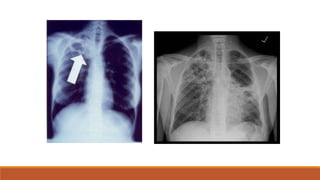

Tipos de tuberculosis

Tuberculosis Primaria,

Complejo primario de

Gohn

Tuberculosis

Secundaria

Imagen cavitada

Iseman MD. Tuberculosis. En: Goldman L. Ausellio D, et Cecil Medicine. 23ava edicion. Philadelfia, Elsevier ;

2007, capitulo 345